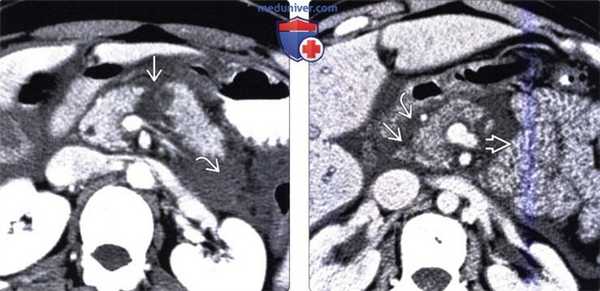

(Слева) На аксиальной КТ с контрастным усилением, выполненной спустя 24 часа после тупой травмы, определяется ишемический некроз тела поджелудочной рядом с линией разрыва, а также скопление жидкости в околопочечном пространстве.

(Справа) На аксиальной КТ с контрастным усилением у этого же пациента определяется едва заметный разрыв головки поджелудочной железы с наличием жидкости в панкреатическом «желобке» Обратите внимание на наличие признаков «шокового кишечника»: утолщение и повышенное контрастное усиление петель тонкой кишки.

(Слева) На аксиальной КТ с контрастным усилением у пациента, получившего травму, определяется гематома на ограниченном участке в области перехода головки в шейку (спереди), наличие которой обусловлено ушибом. Разрывов поджелудочной железы не определяется.

(Справа) На аксиальной КТ с контрастным усилением визуализируется жидкость, окружающая поджелудочную железу Несмотря на то, что признаков разрыва поджелудочной железы на КТ выявить не удалось, наличие жидкости возле нее, особенно в сочетании с повышением сывороточного уровня липазы и амилазы, является крайне подозрительным признаком повреждения поджелудочной железы.